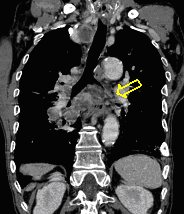

22. Central lung tumor with mediastinal lymphadenopathy. CT coronal and sagittal reconstructions.

70 year old man, COPD, hoarse. Right hilar mass, bronchoscopy was negative.

The larynx is rotated to the right, no motion of the right side of the larynx can be observed, swollen left plica ventricularis area.

CT: 13x11 mm large nodular mass in the left 10th segment. Bilateral hilar lymphadenomegaly with central hypodensity. A 34x21 mm large lymph node conglomeration can be observed in subcarinal location (peripheral contrast enhancement). Lymphadenopathy in the aortopulmonary window (15 mm large), and a 26 mm large lymph node can be observed in paraaortic location above the trachea bifurcation which has an esophagus-compressing effect. In the superior chest aperture there is a 38x28 large fused lymph node conglomerate which causes the left shift of the esophagus and trachea.